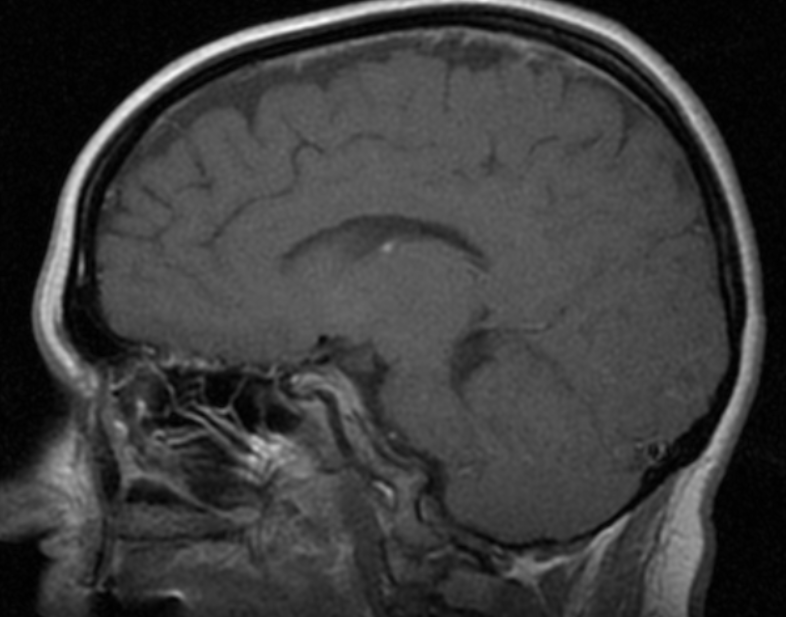

Информация о диссеминированном рассеянном энцефаломиелите